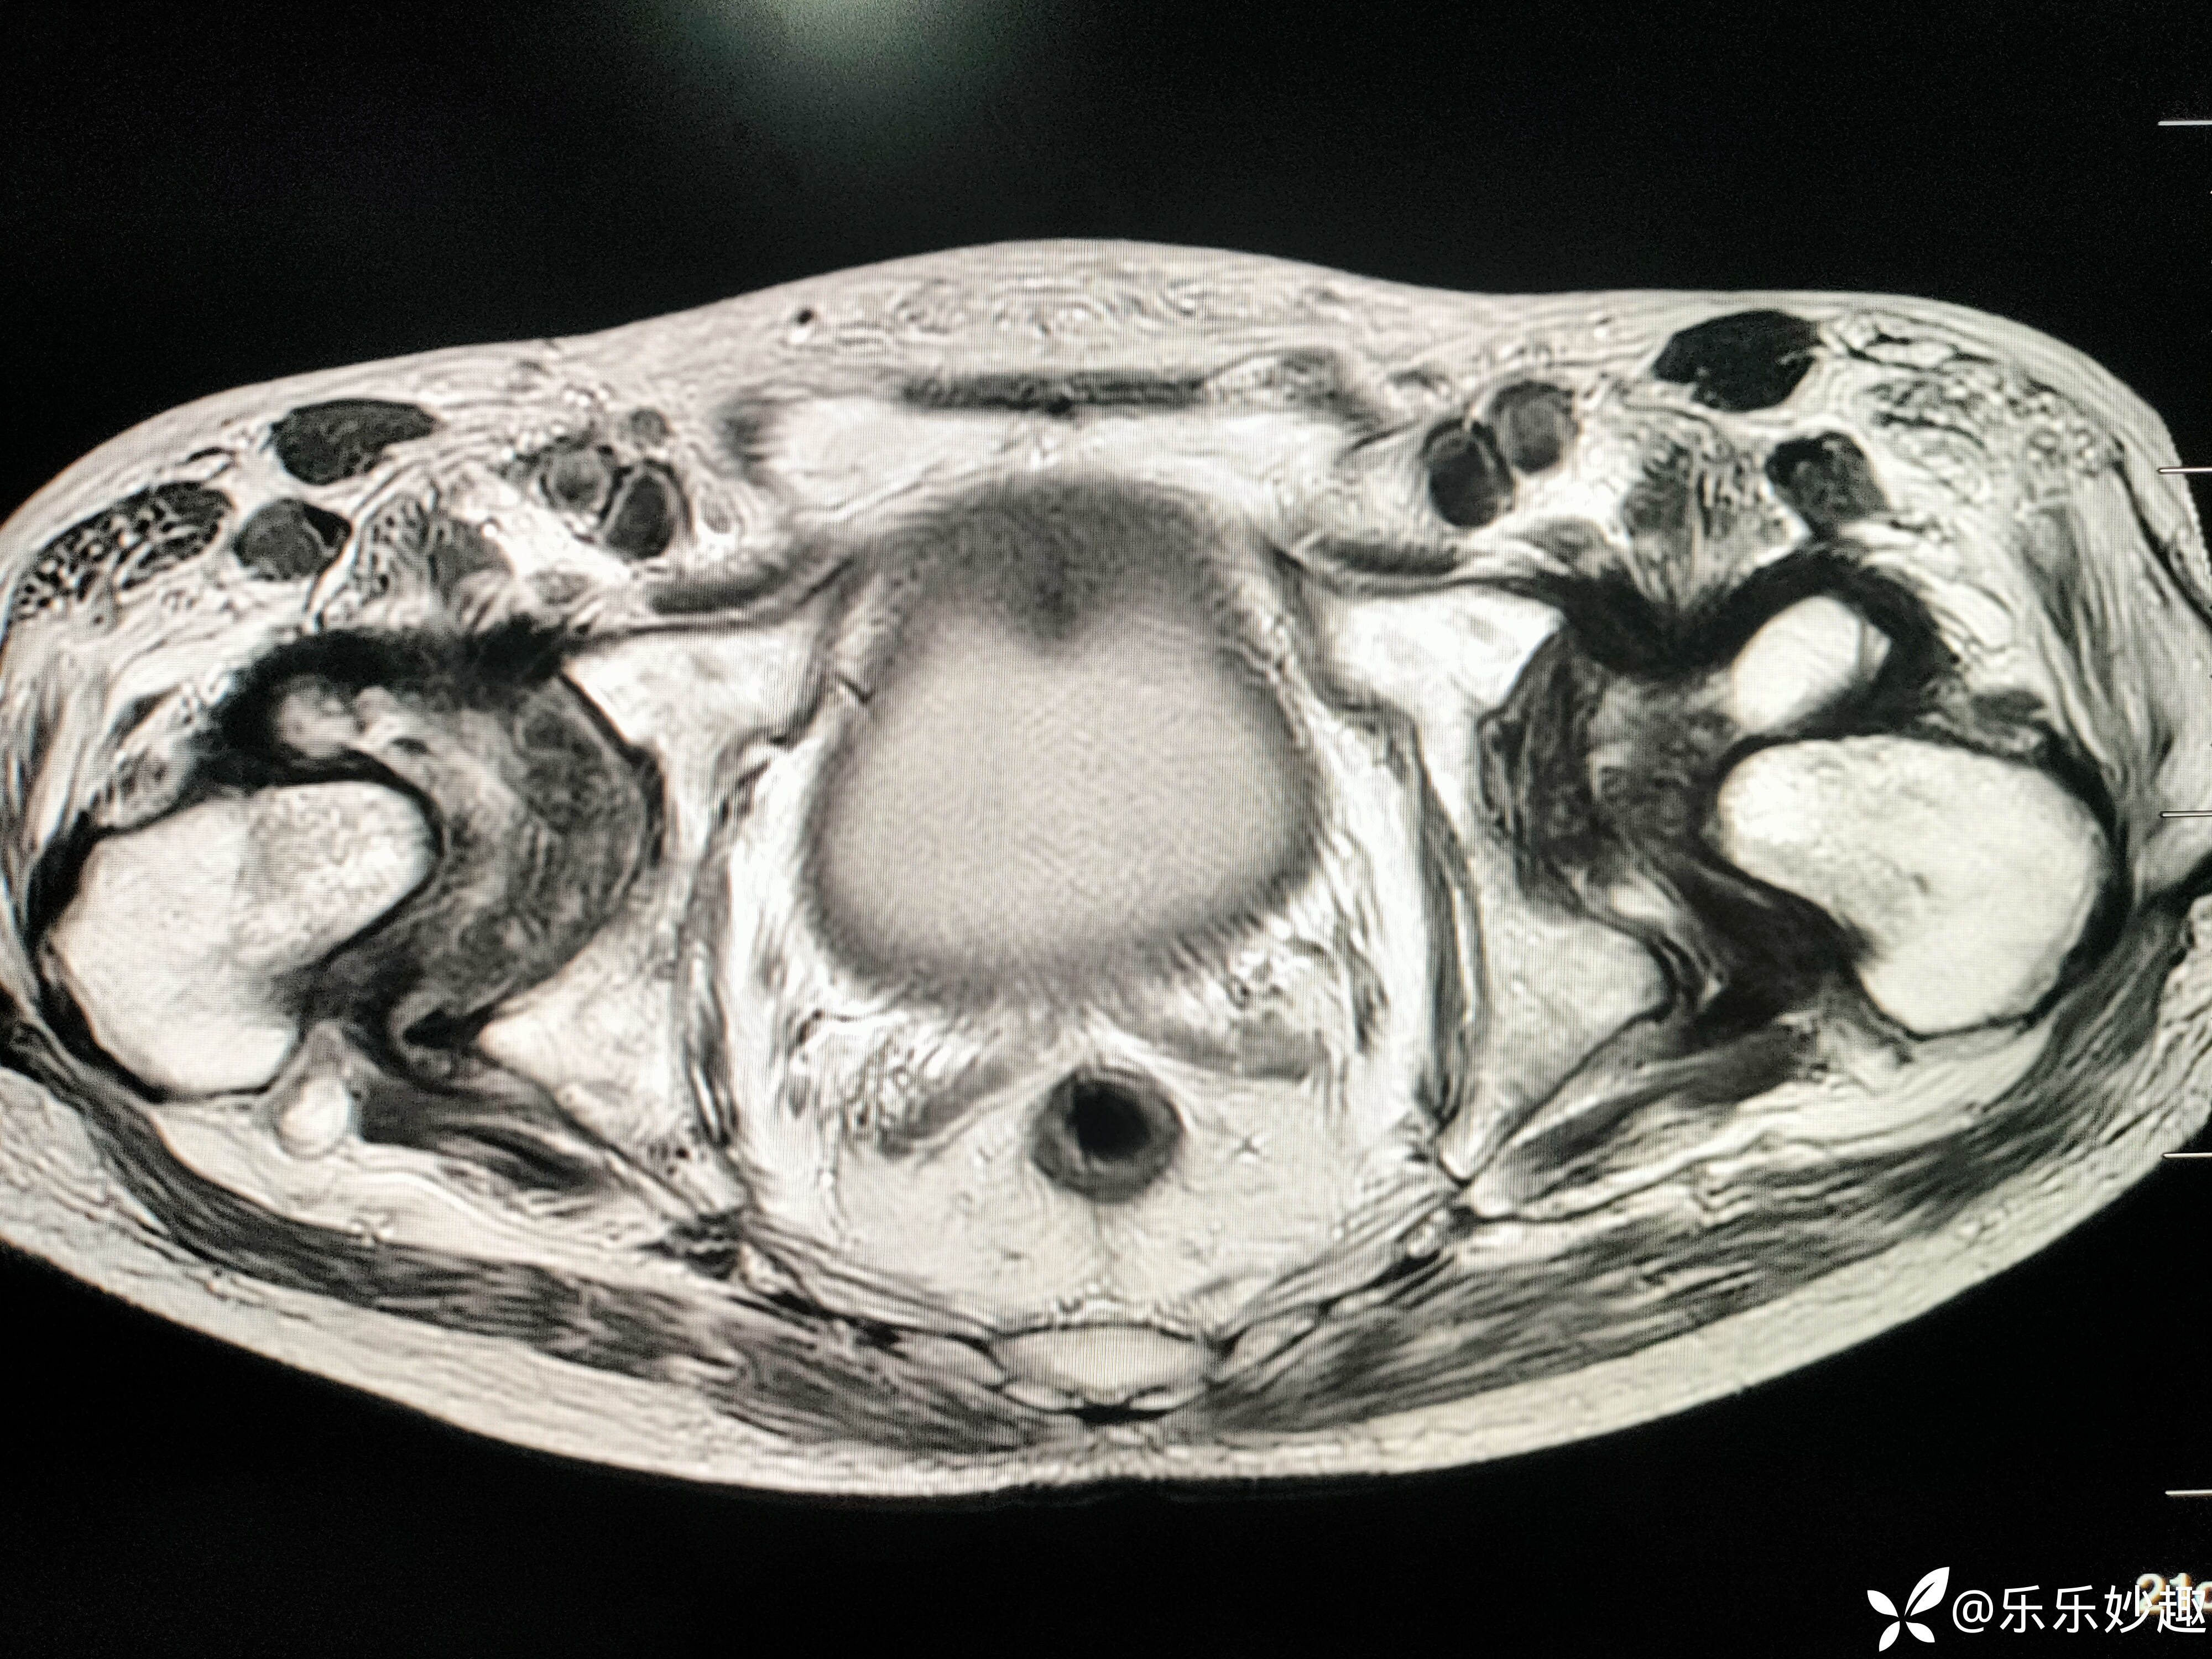

然后做了CT,见下图